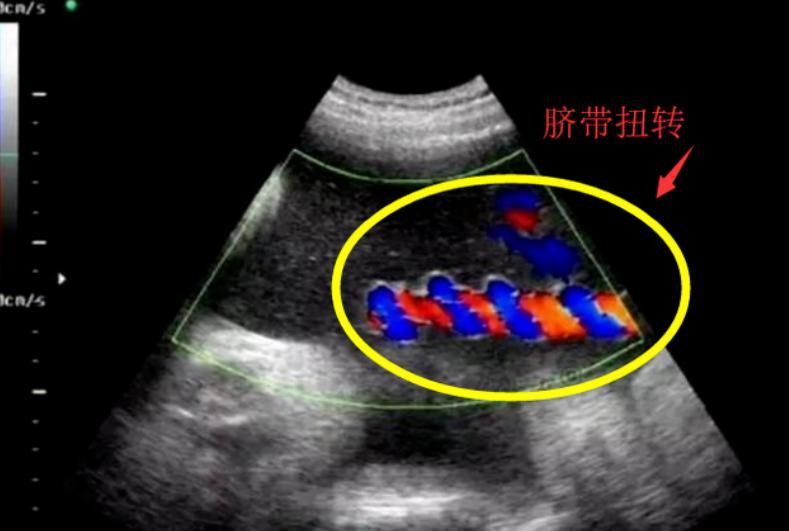

胎兒臍帶扭轉60多圈!臍帶扭轉不是偶然,孕婦該如何避免?

之前網上熱傳一個真實事件:一位孕媽產檢時發現胎兒臍帶可能嚴重扭轉,醫生緊急手術。

取出寶寶時,所有人都倒吸一口涼氣,臍帶緊緊纏繞在孩子身上,扭轉圈數將近六十圈!

肚皮部位已經因缺血發紫。

萬幸,寶寶出生後檢查正常,但這一幕讓無數人直呼“太驚險”。